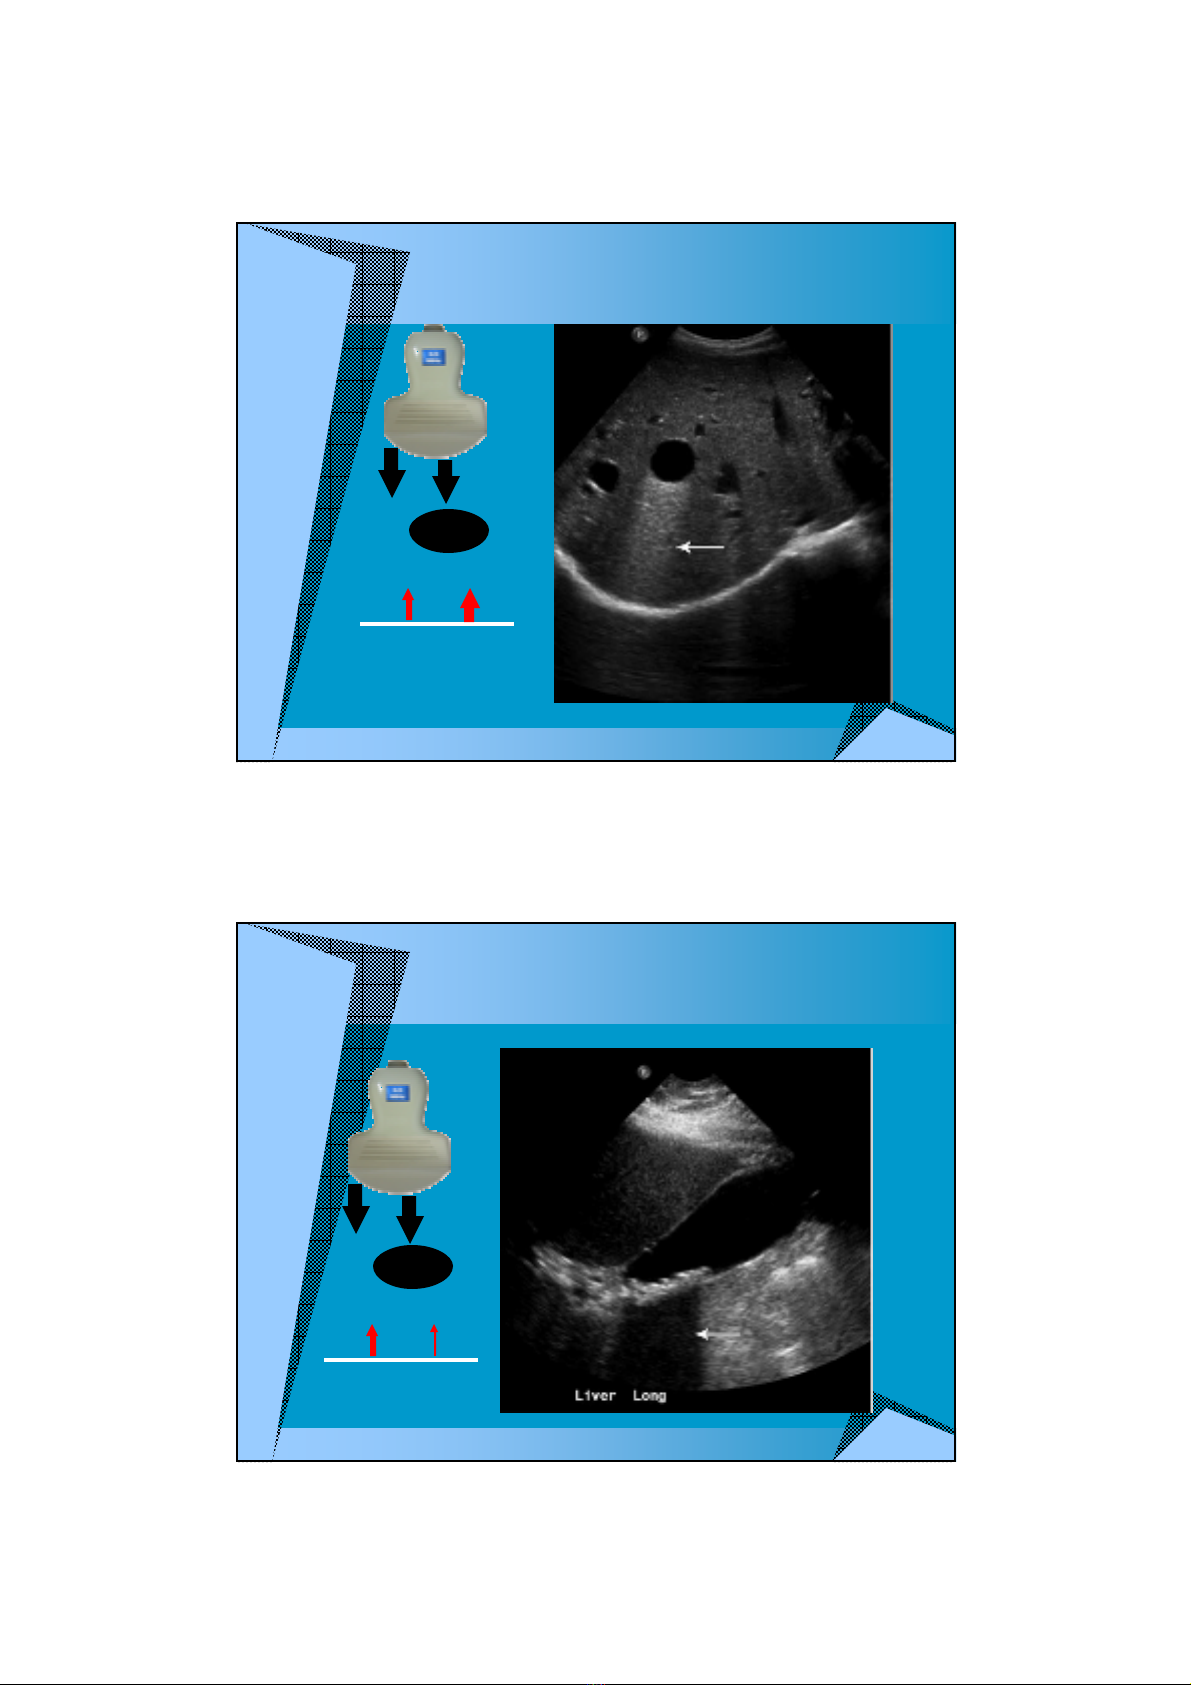

TNG ÂM SAU

Weak

attenuator

NG LNG

Strong